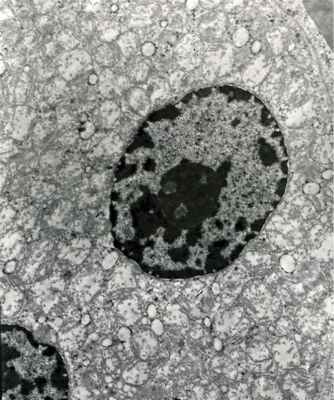

Электронно-микроскопическое исследование

В исследованном материале имеются солидные поля клеток полигональной формы, часть из которых образует папиллярные структуры. Ядра округлой формы с фестончатым контуром или с глубокими инвагинациями. В части клеток наблюдаются ранние признаки некроза: кариорексис, кариопикноз (рис. 2). Рис. 2. Электронно-микроскопические признаки некроза опухолевых клеток. Ядра с неровными контурами; хроматин конденсирован по периферии кариоплазмы. В цитоплазме одних клеток определяются митохондрии и фрагменты цистерн гранулярного эндоплазматического ретикулума; в других — вакуоли, ×4000. В остальных клетках хроматин распределяется по периферии кариоплазмы. В цитоплазме клеток с проявлением ядерных признаков некроза определяется большое количество вакуолей (плазмолиз) с единичными фрагментами коротких цистерн гранулярного эндоплазматического ретикулума, митохондрии, лизосомы (рис. 3). Рис. 3. Электронно-микроскопическая картина в ядре опухолевой клетки. Ядерная мембрана образует глубокие инвагинации; хроматин в виде глыбок, разбросан по всей кариоплазме, ×8000.

В клетках, менее богатых хроматином, можно видеть весь набор обычных органелл с преобладанием митохондрий, выполняющих всю цитоплазму (рис. 4). Рис. 4. Обилие митохондрий, выявленное при электронно-микроскопическом исследовании. Цитоплазма опухолевой клетки содержит большое количество митохондрий, ×6000. На границе клеток встречаются десмосомоподобные контакты. Электронно-микроскопическая картина соответствует диагнозу почечно-клеточного рака с выраженными признаками некроза, что является морфологическим показателем неблагоприятного прогноза [3].